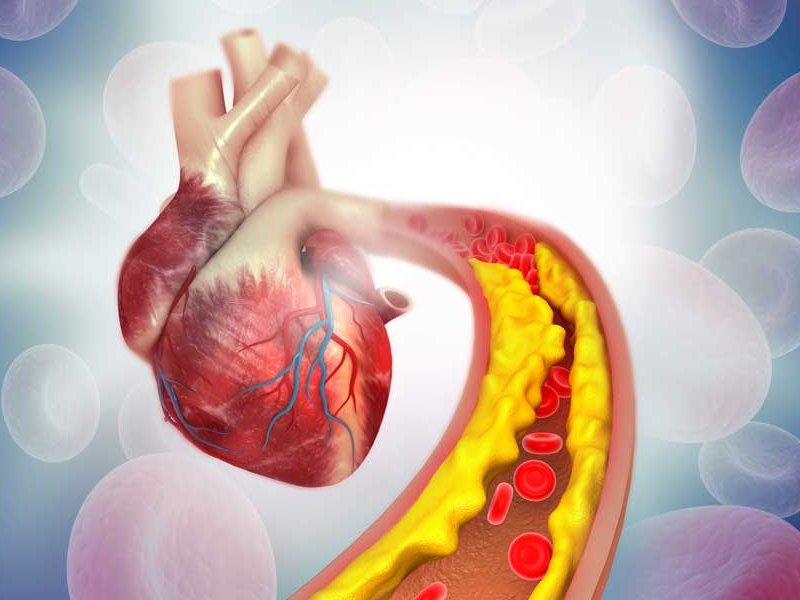

Coronary artery bypass graft (CABG)

CABG is one of the most common types of open heart surgery. The coronary arteries supply the heart with blood. If the arteries become blocked or narrowed due to heart disease, a person may be at risk of a heart attack. The operation involves taking a healthy blood vessel from another part of the body and using it to bypass the blocked arteries